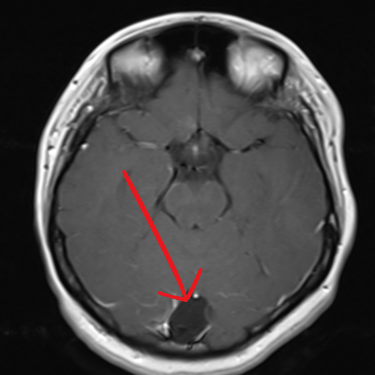

El quiste aracnoideo suboccipital es una lesión benigna de origen congénito, formada por una acumulación de líquido cefalorraquídeo entre las membranas aracnoideas. Aunque en muchos casos puede ser asintomático y detectarse de manera incidental, también puede producir cefalea, mareos, alteraciones del equilibrio o compresión del cerebelo y tronco encefálico. La resonancia magnética (RMN) es el estudio de elección, ya que permite definir la localización, tamaño y sus efectos sobre estructuras adyacentes. Este diagnóstico es clave para establecer la conducta terapéutica, que puede variar entre seguimiento clínico-radiológico o tratamiento quirúrgico en casos sintomáticos o de crecimiento progresivo.